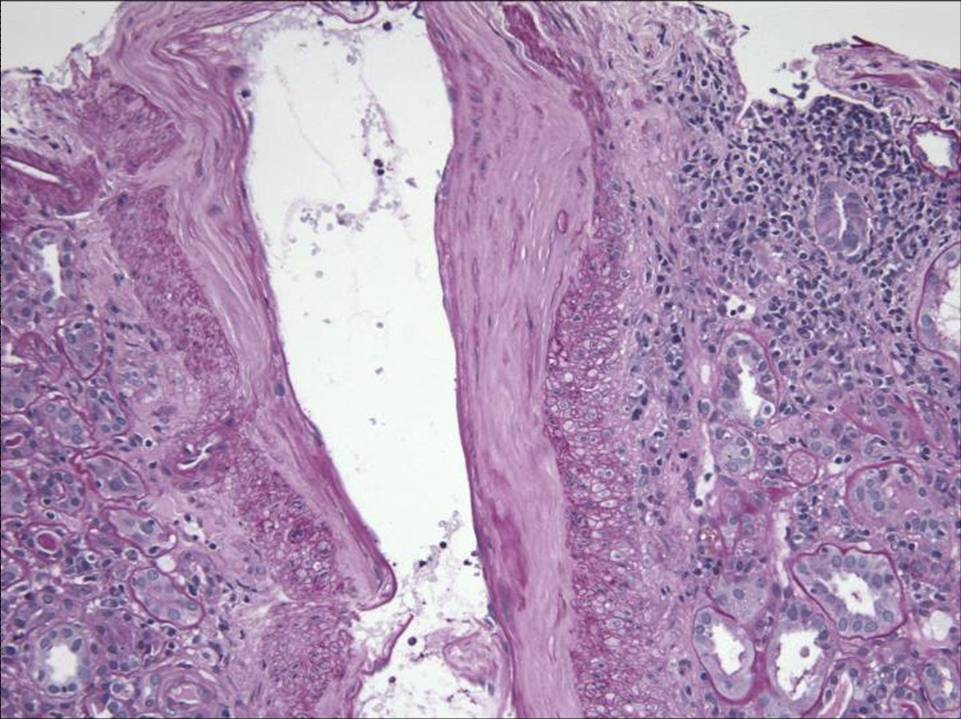

Low power view of the biopsy specimen reveals the presence of an obvious medium-sized vessel – likely an arcuate artery

There were two sections of arcuate artery on the specimen:

The first section showed some arteriosclerosis and some perivascular inflammation but no vasculitis